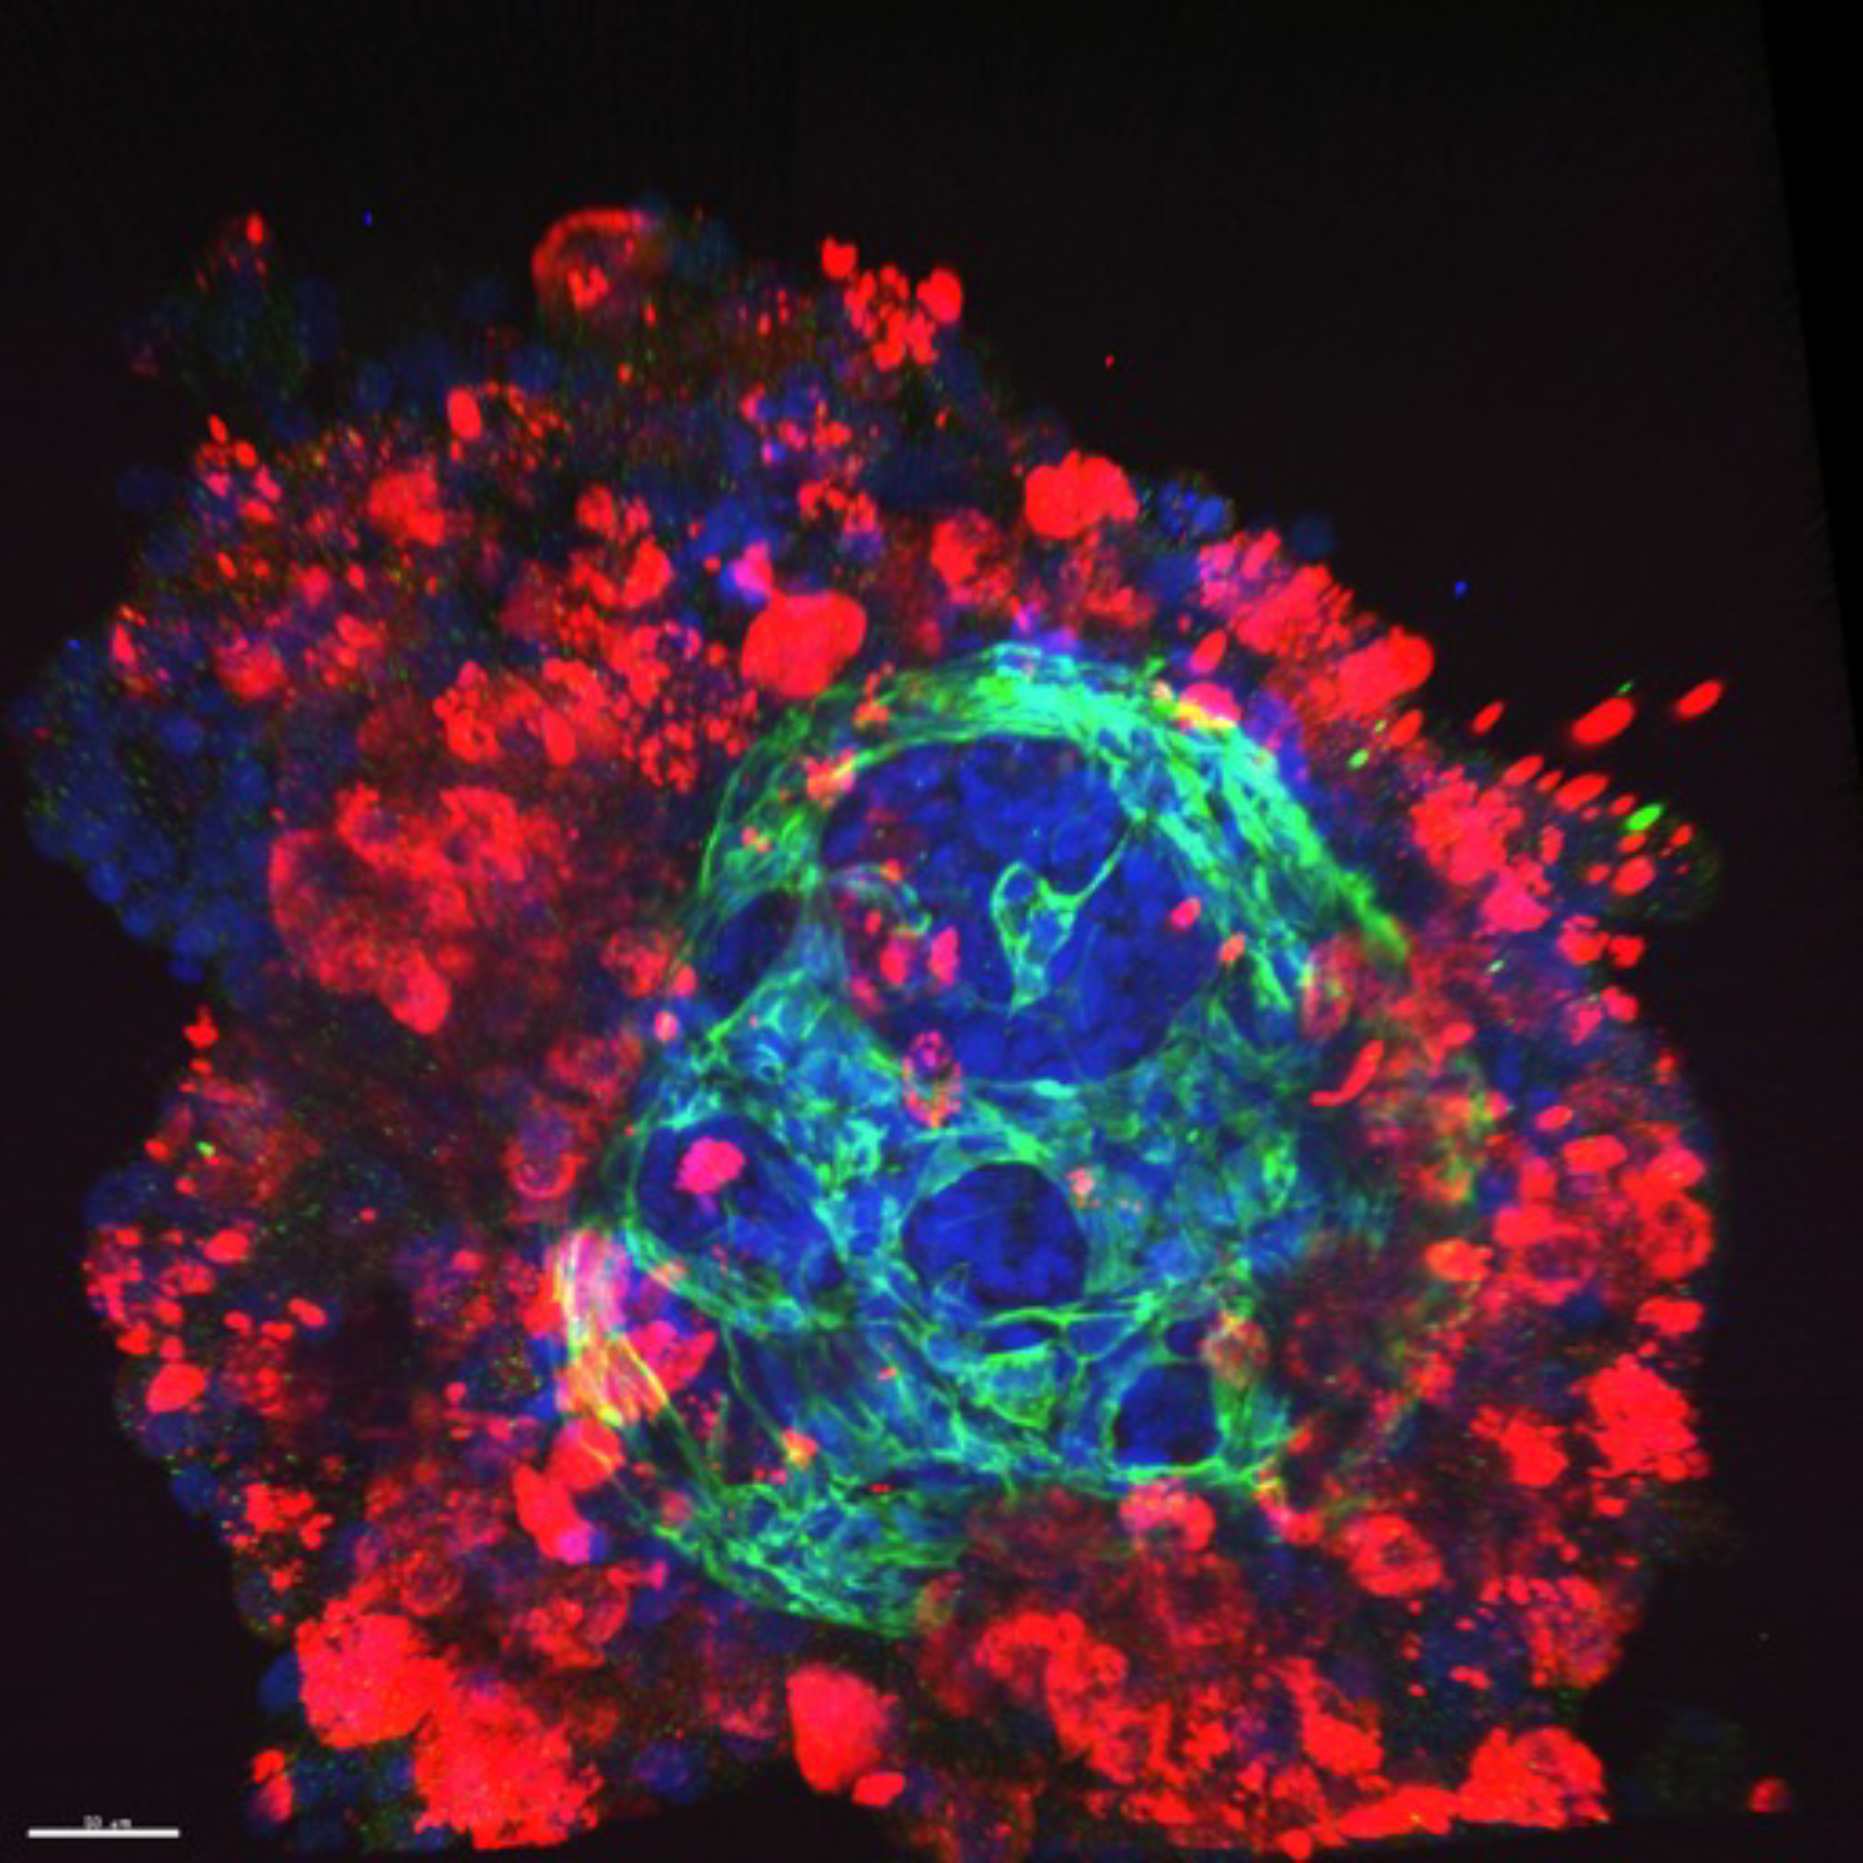

We create high-fidelity human tissues by integrating 3D bioprinting, organ-on-chip microfluidics, advanced biomaterials, AI-driven analytics and modeling. This enables us to predict drug safety and efficacy with unmatched accuracy, reducing time, cost, and reliance on animal testing.

High-fidelity human liver, heart, and other organs for predictive drug screening.

Miniaturized human liver, heart, and other organ models for high-throughput screening.

Reduce the 90% failure rate of animal models with tissue platforms that mimic real human biology.